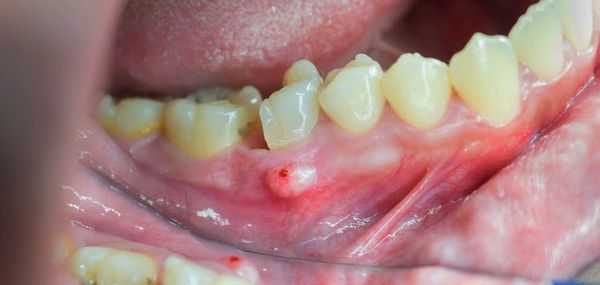

•Гуммозная язва отличается глубиной, неровным, покрытым серовато-желтым плотным налетом

дном. Она окружена валом плотного инфильтрата. При ощупывании дна такой язвы зондом ощущается неровная,

шероховатая поверхность некротизированной кости. По заживлении остается втянутый спаянный с костью рубец,